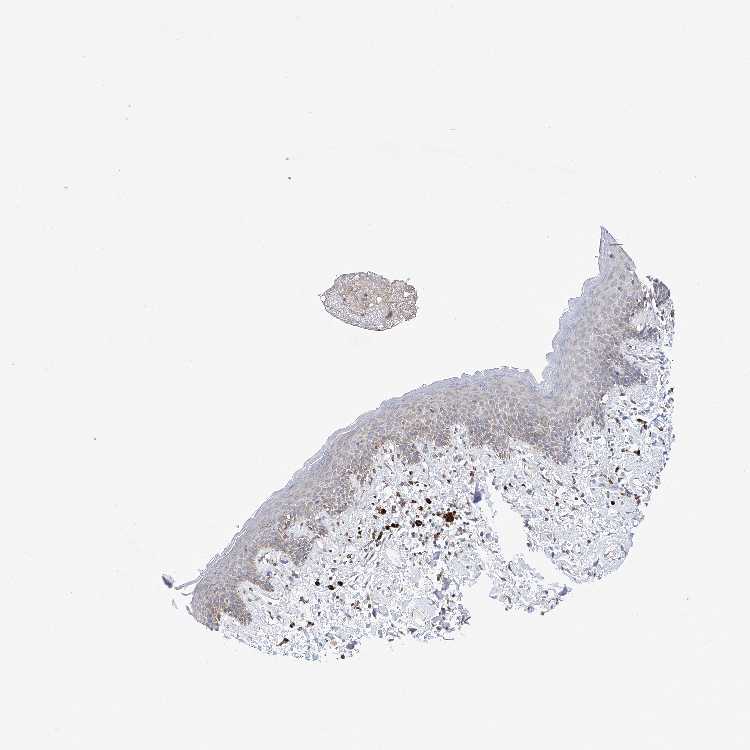

SKIN 1 - Antibody stainingi

Antibody staining in the annotated cell types in the current human tissue is reported as not detected, low, medium, or high, based on conventional immunohistochemistry profiling in selected tissues. This score is based on the combination of the staining intensity and fraction of stained cells.

Each image is clickable and will lead to virtual microscopy that enables deeper exploration of all samples and also displays staining intensity scores, fraction scores and subcellular localization as well as patient and tissue information for each sample.

Antibody HPA003348

Langerhans Not detected

Fibroblasts Not detected

Keratinocytes Low

Melanocytes Not detected